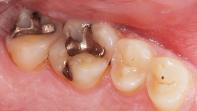

Alte Amalgamfüllung: Bestehende Amalgamfüllungen werden sorgfältig aus dem Zahn entfernt, um eine sichere und biokompatible Alternative einzusetzen.

Amalgam entfernt: Vor der neuen Füllung wird altes Amalgam vollständig entfernt, um den Zahn optimal für die Versorgung mit Komposit vorzubereiten.